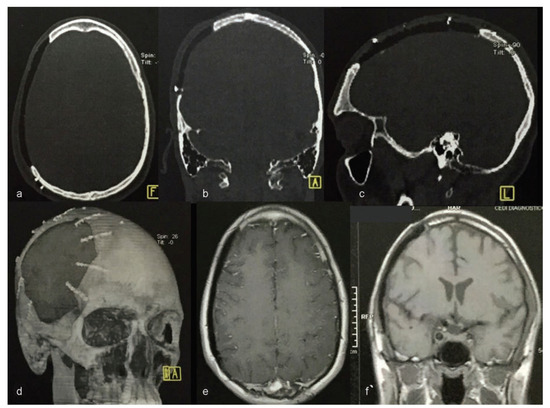

Figure 11. Postoperative computed tomography (ad) and magnetic resonance imaging (e,f) view. No inflammatory features.